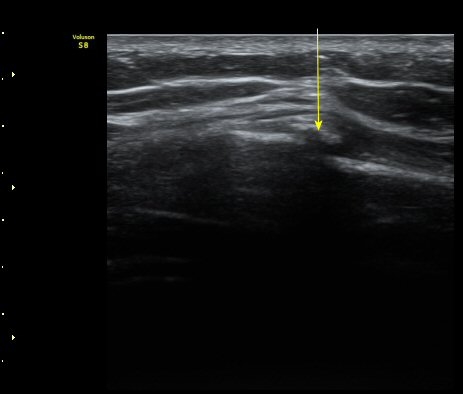

ÇÑ´Þ ÈÄ ÃßÀû°Ë»ç

Á¾´Ü¸é°Ë»ç¿¡¼­ °¡°ñ Çü¼ºÀÌ °üÂûµÊ(formation of callus)   »çÁø 3

°¥ºñ»À Ⱦ´Ü¸é°Ë»ç¿¡¼­ °¡°ñ Çü¼ºÀÌ °üÂûµÊ(formation of callus)  »çÁø 4